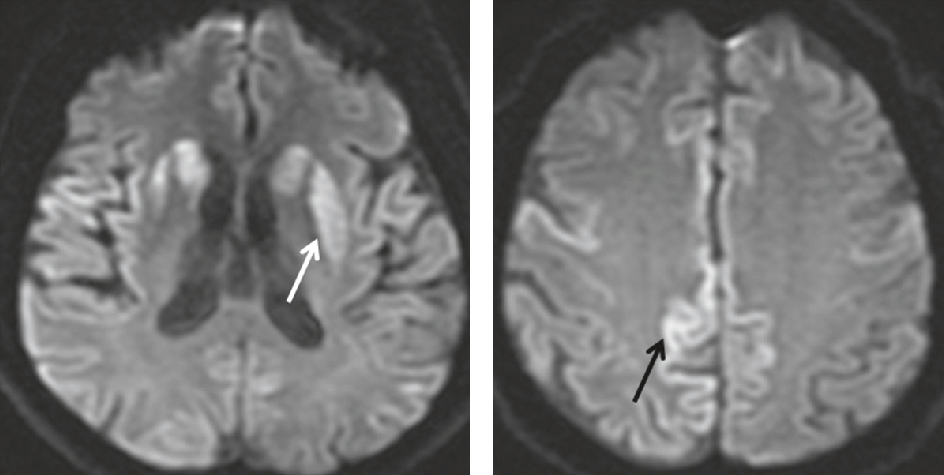

• • discuter un EEG, une ponction lombaire pour étude du LCS en cas d’hyperthermie faisant suspecter une encéphalite ou en cas de suspicion de maladie de Creutzfeldt-Jakob : recherche de protéine 14-3-3 dans le LCS, d’hypersignaux corticaux et des ganglions de la base en IRM de diffusion (fig. 18.4) et d’activité périodique à l’EEG.

Fig. 18.4 Figure Hypersignaux des ganglions de la base et notamment du putamen gauche (flèche blanche), ainsi que du cortex (flèche noire) dans une maladie de Creutzfledt-Jakob (séquence T2/FLAIR).

L'image montre des hypersignaux des ganglions de la base, en particulier du putamen gauche (indiqué par une flèche blanche sur l'image A), ainsi que du cortex (indiqué par une flèche noire sur l'image B) dans le cadre d'une maladie de Creutzfeldt-Jakob. Ces images sont obtenues par séquence T2/FLAIR, une technique d'imagerie par résonance magnétique (IRM) qui permet de visualiser les anomalies du cerveau. La maladie de Creutzfeldt-Jakob est une maladie neurodégénérative rare et fatale, caractérisée par une détérioration rapide des fonctions cognitives et motrices. Les hypersignaux observés sur ces images sont des indicateurs de lésions cérébrales spécifiques à cette maladie. Le putamen et le cortex sont des régions du cerveau impliquées dans le contrôle des mouvements et des fonctions cognitives. Les anomalies dans ces zones peuvent expliquer certains des symptômes observés chez les patients atteints de la maladie de Creutzfeldt-Jakob, tels que des troubles de la mémoire, des changements de comportement et des difficultés motrices. Ces images sont cruciales pour le diagnostic et la compréhension de cette maladie.